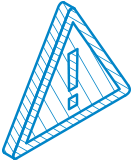

유로진은 발기 전/후 상태를 정밀히 측정하여

확대 후 발기 시 턱짐현상이나

귀두·음경 뒤쪽의

결손 현상 위험을 현저히 줄이고 있습니다.

실리콘보형물

유로진 보형물 확대는 다양한 종류와

크기의 실리콘 제품들이 있어서

본인의 취향과

음경의 상태에 따라 선택이 가능합니다

특 - 징

- KFDA 승인을 받은 인체용 실리콘

- 선호도·성기크기에 맞는 재료 선택 가능

- 저렴한 비용 및 교체나 제거가 용이함

보형물 종류

프리미엄 T링

귀두 부분은 물론 몸통 부분까지 보완해주는

보형물로 비교적 형태와 착용감이 자연스럽고

길이연장 효과를 얻을 수 있는 T링